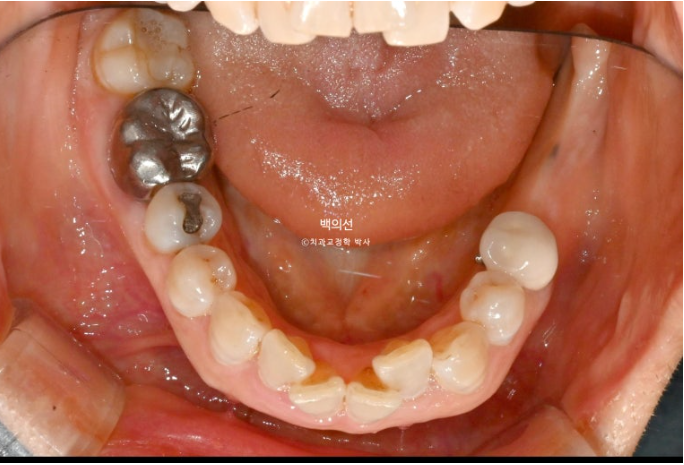

좌측 아래는 어금니가 빠진 지 오래된 상태입니다.

임플란트가 필요한 부분을 장기간 방치하면 대합치가 조금씩 솟아 내려오게 됩니다.

아래 앞니는 치아가 많이 겹쳐져 있습니다.

특히 가운데 앞니와 옆 앞니는 50% 정도가 겹쳐진 상태

치아가 많이 겹쳐진 부위는 가지런히 배열이 끝나면 블랙트라이앵글이 크게 생깁니다.